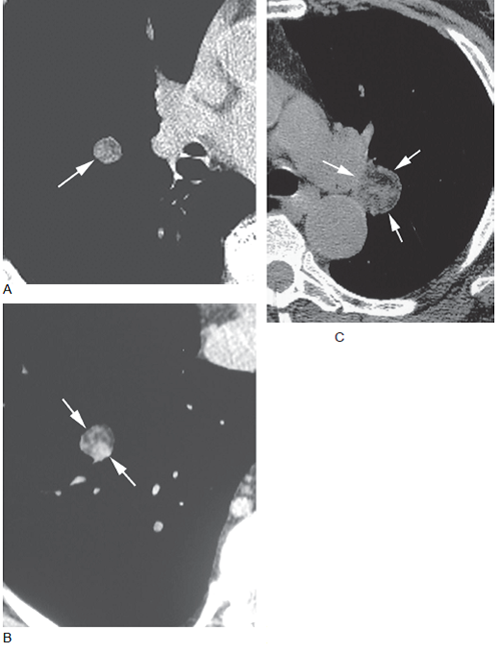

图2 两例患者中钙化的错构瘤

A. 错构瘤局灶性的钙化( 箭头),结节呈圆形,边界清楚;B. 错构瘤呈爆米花样钙化( 箭头),这个征象来自于肿瘤内含软骨的结节的钙化